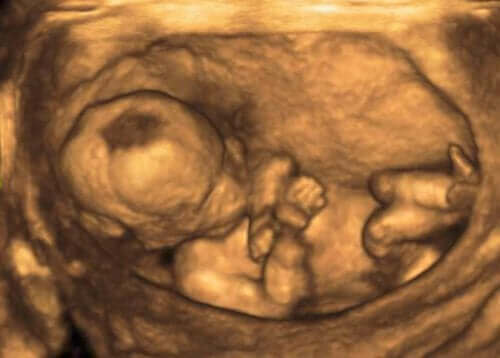

Tıp uzmanları, bu değişimleri genellikle amniyotik sıvının hacmini ölçmek için kullandıkları bir ultrason prosedürü ile tespit ederler. Bunu amniyotik sıvı indeksi (AFI) aracılığıyla yaparlar.

Bu bilgiyi elde etmek için uzman, rahmi, santimetre ölçü birimini kullanarak dört engellenmemiş çeyreğe böler. Normal bir amniyotik sıvı endeksi, 3 – 8 inç (8 ve 21 cm) arasındadır.